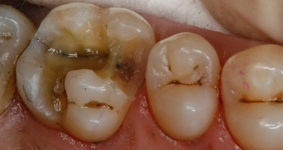

Günümüzde hastaya objektif ve verimli tedavi ortamı sağlamak diş hekimleri için birincil önceliktedir. Özellikle pulpaya yakın bölgede çürüğün değerlendirilmesi- tespiti- diş hekimleri için önemlidir.

Uzun dönemde çürük tespitinde ikilemlerle karşılaşılabilir. Pulpaya yaklaşıldıkça dokular daha yumuşak hal alır. Çürük tespit boyaları bu alanda memnun edici sonuçlar vermezler, hem pulpaya yakınlıktan dolayı hem de mine dentin kesişme noktalarında sahte pozitif sonuçlar verebilirler. Boyayarak çürük tespit yönteminin başka bir dezavantajı ise bitişme alanlarını kalıcı olarak lekeleyebilmesidir. El aletiyle doku kazıma yöntemi ise sağlıklı doku kaybına da sebep olacağından risk taşır.

Modern FACE (Fluorescence Aided Caries Excavation) metodu ise diş hekimine karar verme ve değerlendirme sürecinde yeni bir perspektif kazandırır. Bir ışık çubuğu yardımıyla kaviteyi aydınlatarak çürük tespiti yapmak hızlı ve kolay bir yöntemdir. Bakteriler sebebiyle enfekte olmuş dentin alanı florasan ışığı yardımıyla açıkça görünür, ki bu kesin tedavi için gereklidir.

Sistem bir ışık çubuğundan ve gözlüğünüzün üzerine de takabileceğiniz filtreli bir gözlükten oluşur. Facelight ışık probunui kullanarak kaviteyi aydınlatırsınız, ışık çubuğunun kullanımı polimerizasyon cihazlarının kullanımı gibidir. Özel gözlüğüyle bakıldığında bakterilerin metabolik ürünleri (porfirinler) sağlıklı dokudan farklı olarak kırmızı görünür. Diş hekimi çürük dokuyu rahatlıkla görebilir.

Florans ışığı altında filtreli gözlükle yapılan değerlindermede sağlıklı doku yeşil, bakteriyle enfekte olmuş doku kırmızı görünür.

Deneyimler gösterdi ki çürük bölgesine Facelight ile bakıldığında görebileceğiniz daha fazla şey vardır. Klasik yöntemlerle ince çürük ya da enfekte alanları tespit etmeniz güçtür.

14 Hasta üzerinde yapılan araştırmalarda 67 çürük kavite incelendi. Standart ekskavasyon işleminin ardından ekskavatör yardımıyla yapılan değerlendirmede kavitelerin tümünün çürükten arındırıldığı sonucuna varıldı. Ancak Facelight ile tekrar kontrol edilen kavitelerin 14 ünde enfekte alanların varlığı görüldü. Hatta 11 kavite tamamen çürük dokuydu.Bu araştırmalar da göstermektedir ki Facelight efektif, güvenli ve verimli bir tedaviye hızlı ve kolay bir şekilde imkan tanır.